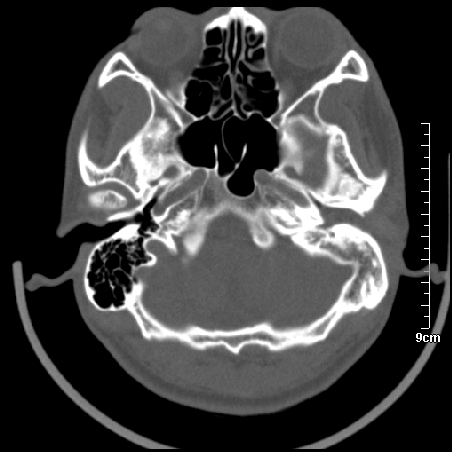

病例1

m/46y 头晕.耳鸣半月余 有乳突炎病史

左侧板障型乳突。

左侧慢性中耳炎伴胆脂瘤形成。